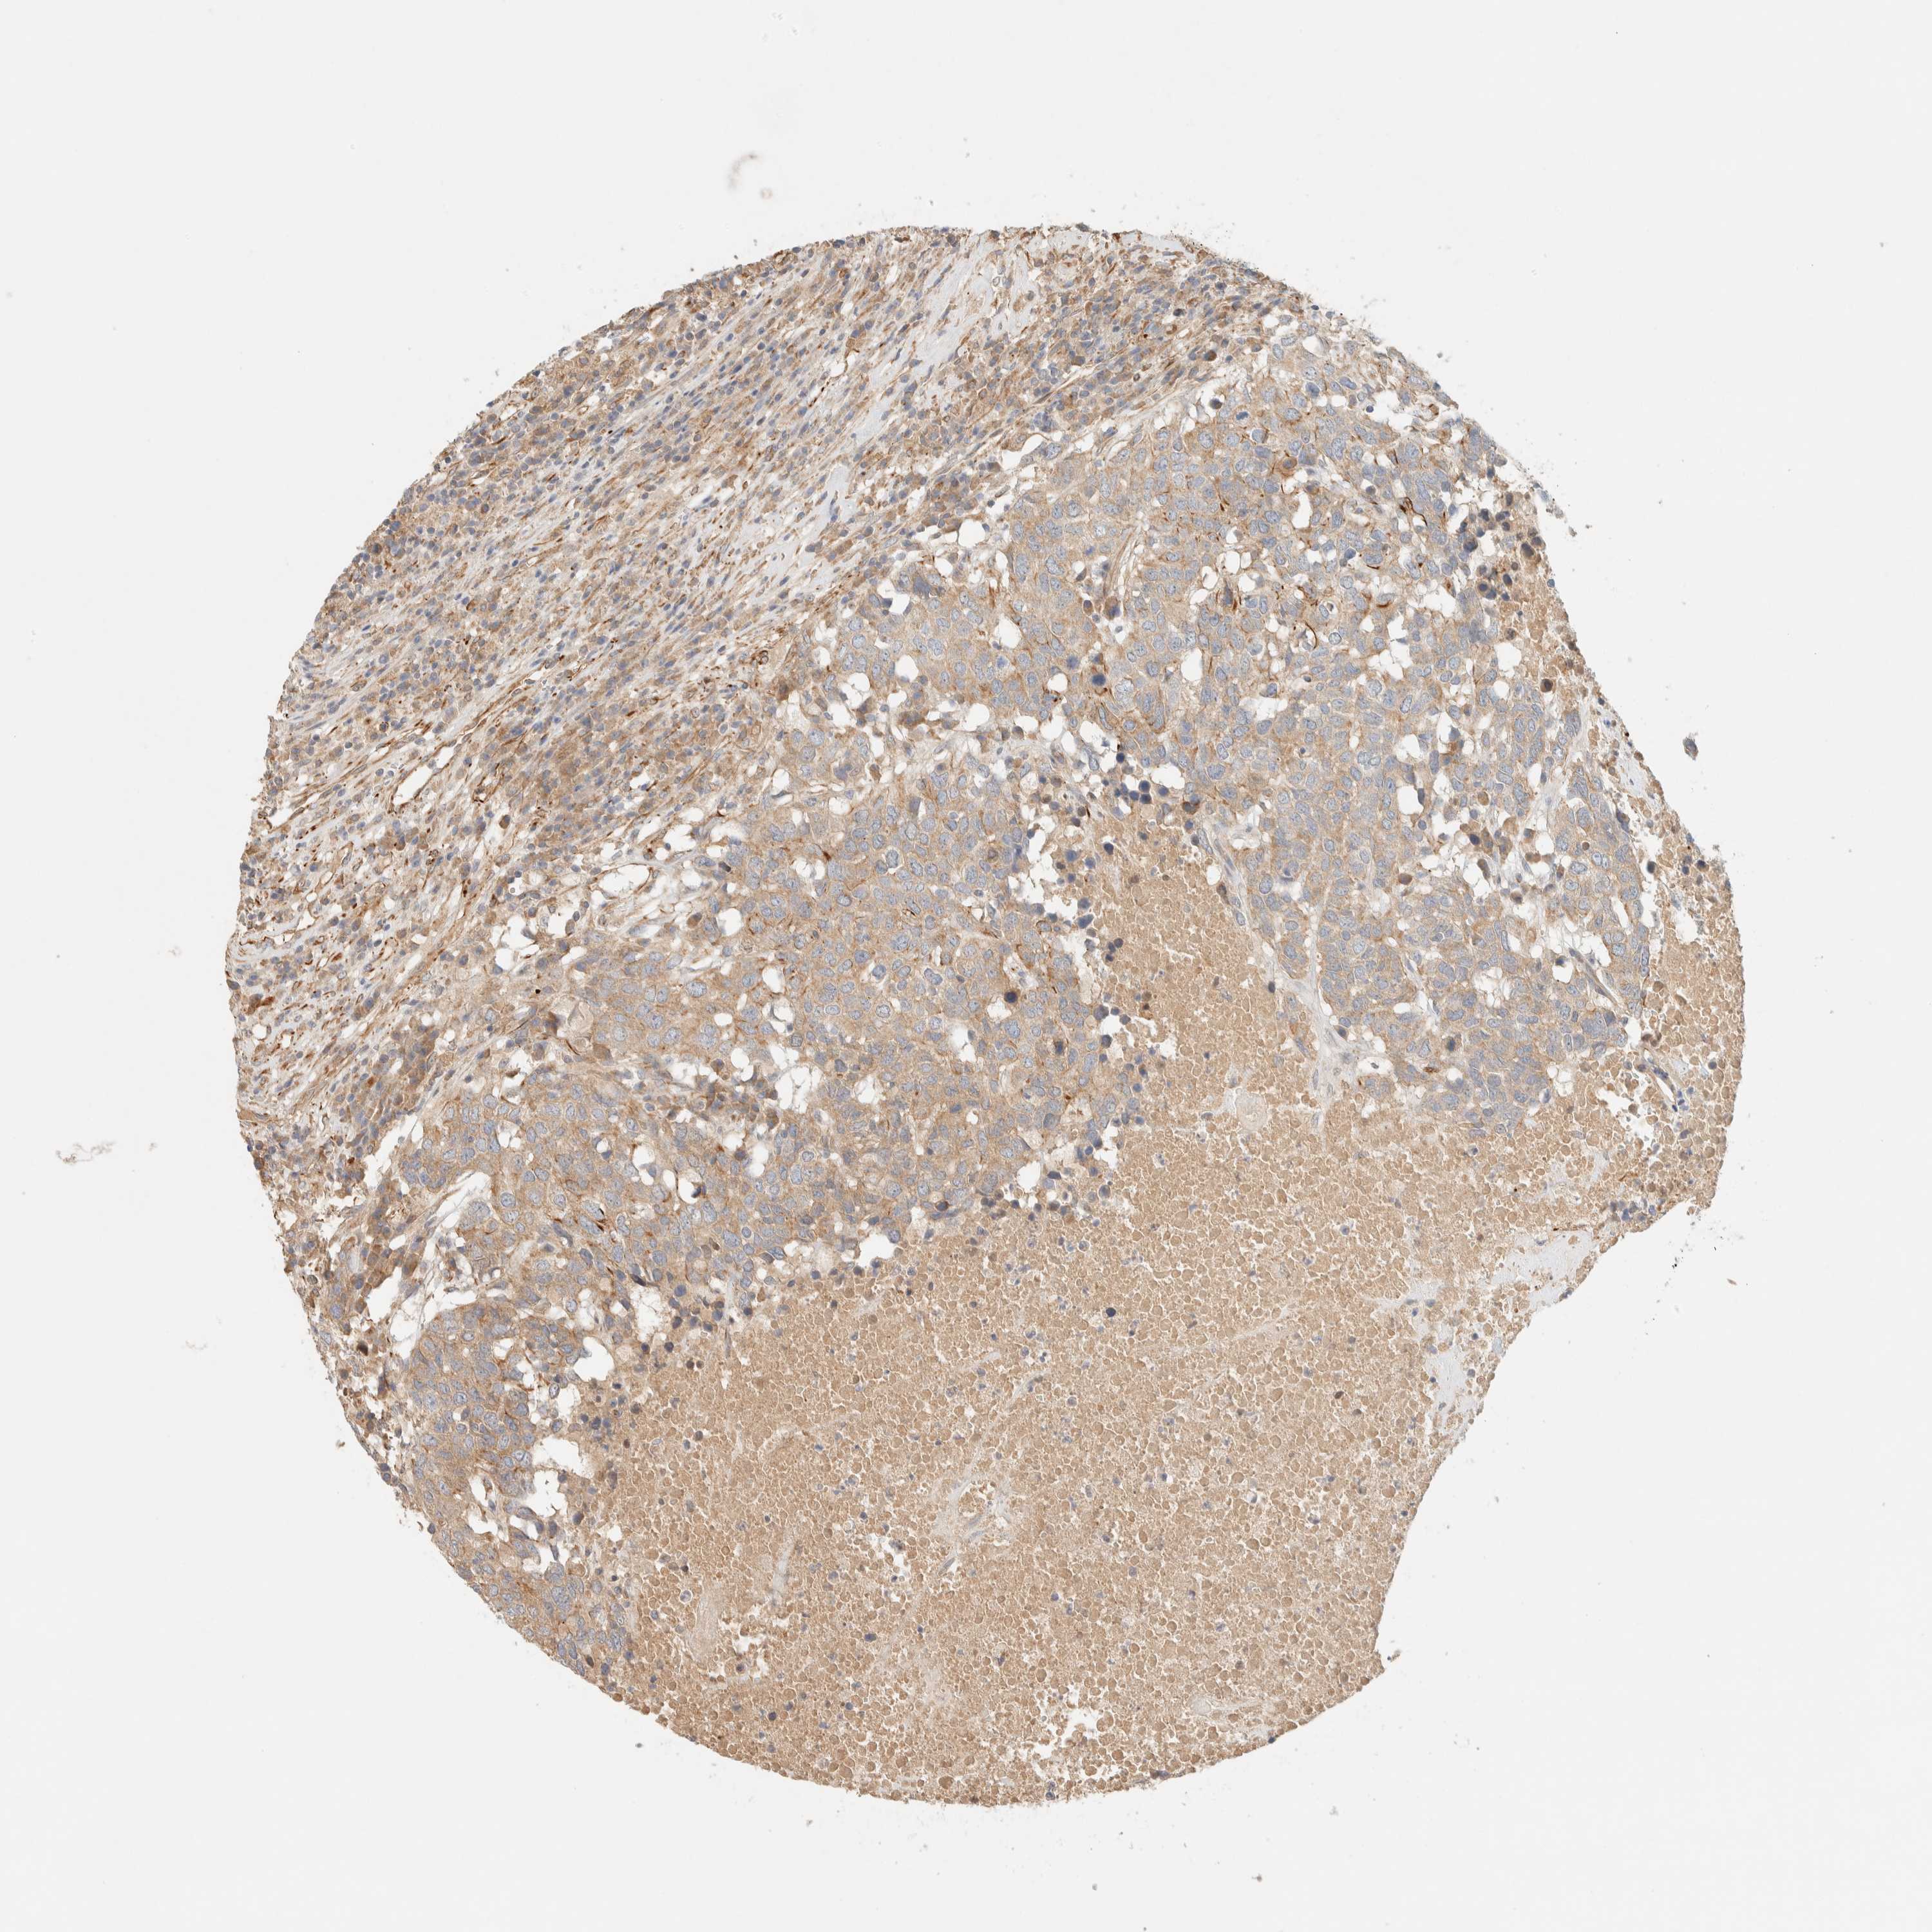

HEAD AND NECK CANCER - Protein expressioni

A mouse-over function shows sample information and annotation data. Click on an image to view it in a full screen mode. Samples can be filtered based on level of antibody staining by selecting one or several of the following categories: high, medium, low and not detected. The assay and annotation is described here.

Note that samples used for immunohistochemistry by the Human Protein Atlas do not correspond to samples in the TCGA dataset.

Antibody stainingi

Antibody staining in the annotated cell types in the current human tissue is reported as not detected, low, medium, or high, based on conventional immunohistochemistry profiling in selected tissues. This score is based on the combination of the staining intensity and fraction of stained cells.

Each image is clickable and will lead to virtual microscopy that enables deeper exploration of all samples and also displays staining intensity scores, fraction scores and subcellular localization as well as patient and tissue information for each sample.

Antibody HPA001869

Antibody HPA023882

Squamous cell carcinoma, NOS

Neoplasm, malignant, NOS

Adenocarcinoma, NOS

Squamous cell carcinoma, metastatic, NOS